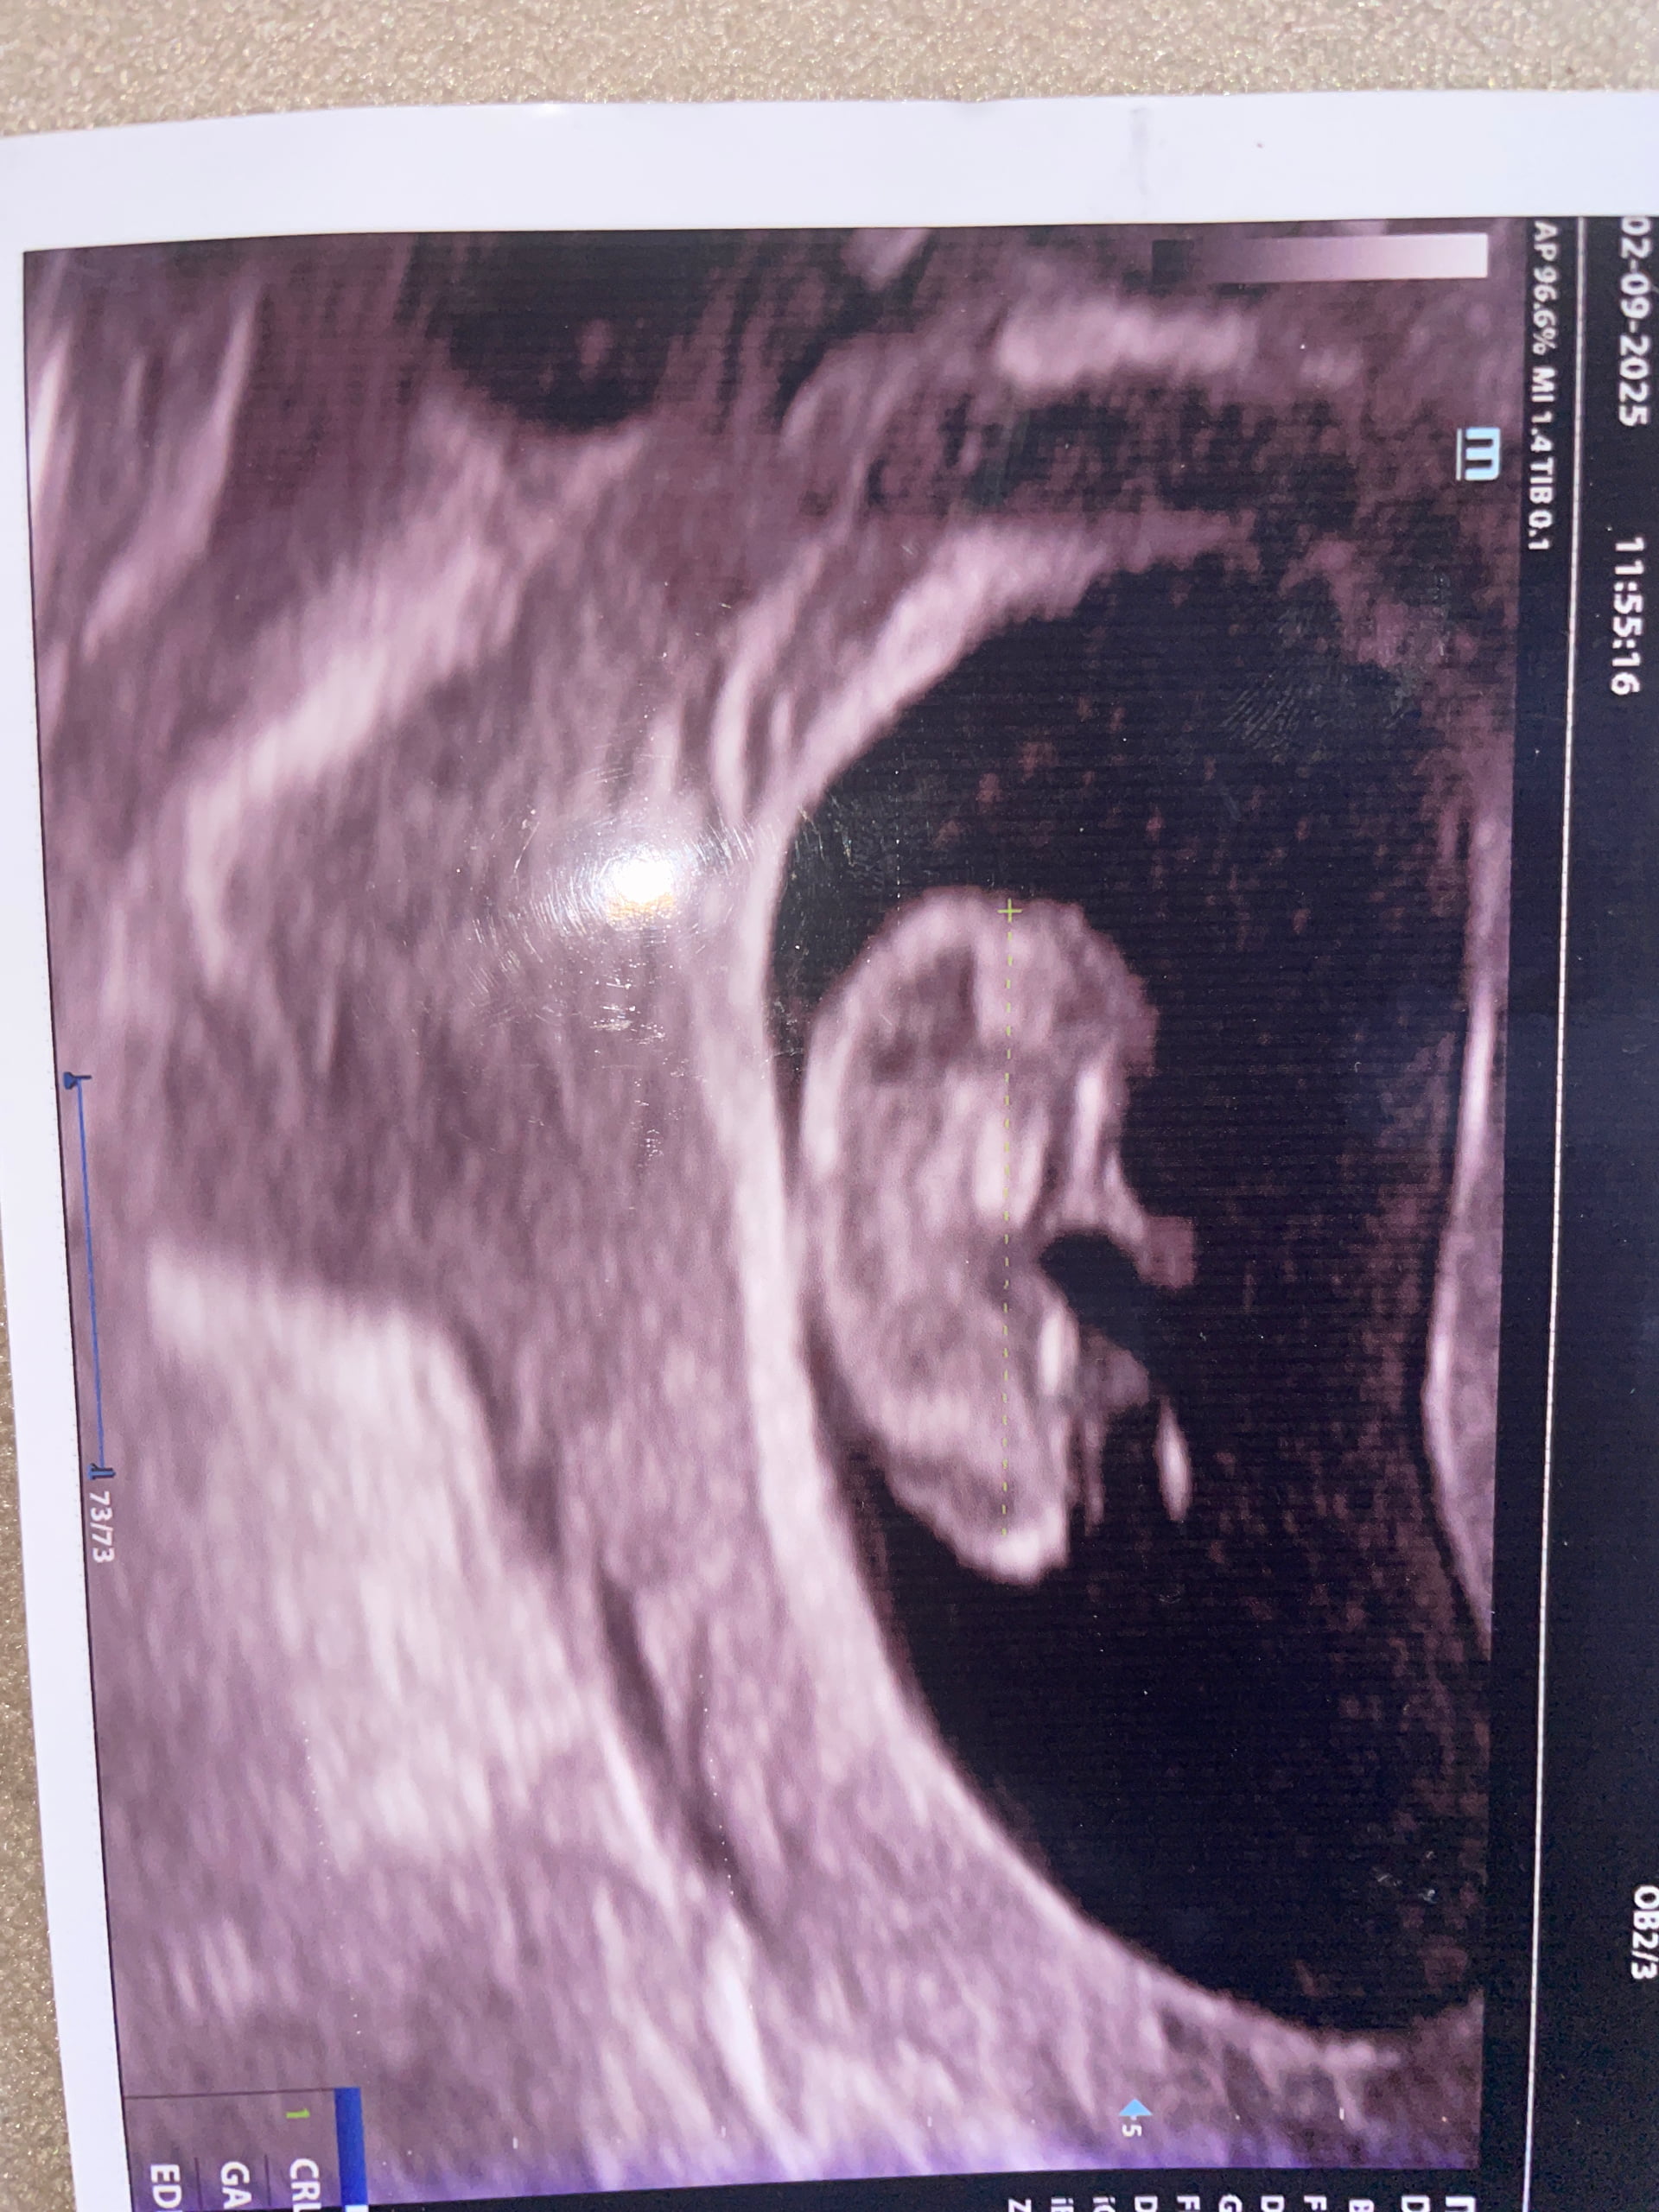

Doktora ben sordum keseye göre cinsiyet belirleme oluyormu diye hayır dedi öyle bişi yok dedi

Benim kesem yuvarlaktı ama oğlum olucak, kese şekline göre cinsiyet yorumlamak halk inanışı tamamen kanıtlanmış hiçbir bilimsel tarafı yok, doktorunuz söyleyene kadar bekleyin bence böyle şeylere inanıp umut bağlamayın ![]()

Ya tabiki bilimsel bi kaniti yok ama insan cinsiyet öğrenene kdr mersk ediyo sanki birinin dedigine hemen inaniyomuyuz annenin hissinden de anlasilabilir bende tahminde bulundum genelde kese şekli uzun olunca erkek giyolar o yuzden tahmini erkekten yana yaptım yoksa benimkinin keseside sekilsizdi ve kızım olucak belli olmuyo yani